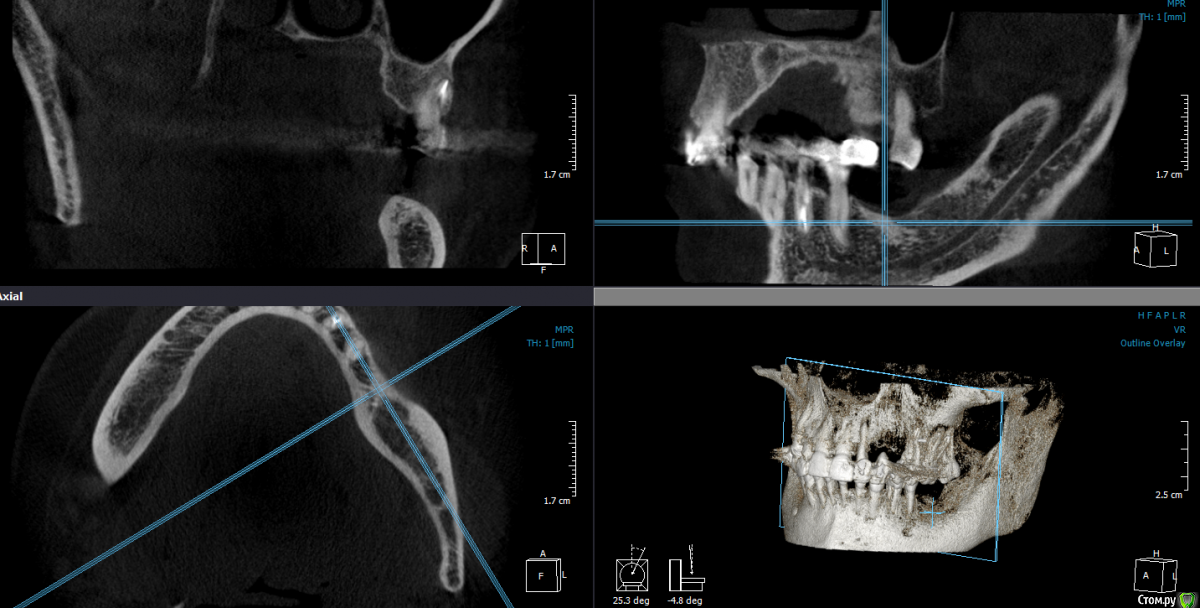

Популярный пост Dantist55 Опубликовано 22 декабря, 2014 Автор Популярный пост Поделиться Опубликовано 22 декабря, 2014 Через 5 месяцев... 21 Ссылка на комментарий

Mane Опубликовано 22 декабря, 2014 Поделиться Опубликовано 22 декабря, 2014 в целом хорошо. но нет деталей где я смогу понять что качественно отработали: 1) кт срезы до и после с замерами чтоб было понятно на сколько нарастили 2)кт срезы с установленными имплантами чтоб было понятно какие болты удалось установить и стало чтоб всем понятно для чего наращивали - ведь вы растили в высоту и в ширину. 3) фото на этапе установленных имплантов - соотношение платформы импланта и уровня кости - заглубили или нет - если да то насколько. Ориентировались ли на будущий зенит зуба. мне понравилось. но чуйка что есть гиперлечение - думаю можно было болты и костную пластику совместить. Растить по высоте я скорее всего бы не стал. 1 Ссылка на комментарий

SDC Опубликовано 22 декабря, 2014 Поделиться Опубликовано 22 декабря, 2014 Через 5 месяцев...Мне не понравилось просветление в 3 квадранте. Крутили КТ? Что это? Ссылка на комментарий

Dantist55 Опубликовано 22 декабря, 2014 Автор Поделиться Опубликовано 22 декабря, 2014 в целом хорошо. но нет деталей где я смогу понять что качественно отработали: 1) кт срезы до и после с замерами чтоб было понятно на сколько нарастили 2)кт срезы с установленными имплантами чтоб было понятно какие болты удалось установить и стало чтоб всем понятно для чего наращивали - ведь вы растили в высоту и в ширину. 3) фото на этапе установленных имплантов - соотношение платформы импланта и уровня кости - заглубили или нет - если да то насколько. Ориентировались ли на будущий зенит зуба. мне понравилось. но чуйка что есть гиперлечение - думаю можно было болты и костную пластику совместить. Растить по высоте я скорее всего бы не стал.КТ посмотрю позже на работе - я в отпуске.По высоте добавляли чтобы зубы не получились большими.Импланты не заглублял, т.к. у XIVE полированная фаска.Насчет гиперлечения может Вы и правы. Эту работу я сделал сразу после приезда от Кури. 2 Ссылка на комментарий

Dantist55 Опубликовано 22 декабря, 2014 Автор Поделиться Опубликовано 22 декабря, 2014 Мне не понравилось просветление в 3 квадранте. Крутили КТ? Что это?Перед имплантацией крутил-все было норм. Ссылка на комментарий

SDC Опубликовано 22 декабря, 2014 Поделиться Опубликовано 22 декабря, 2014 Перед имплантацией крутил-все было норм.Значит так эксклюзивно фонит. Ссылка на комментарий